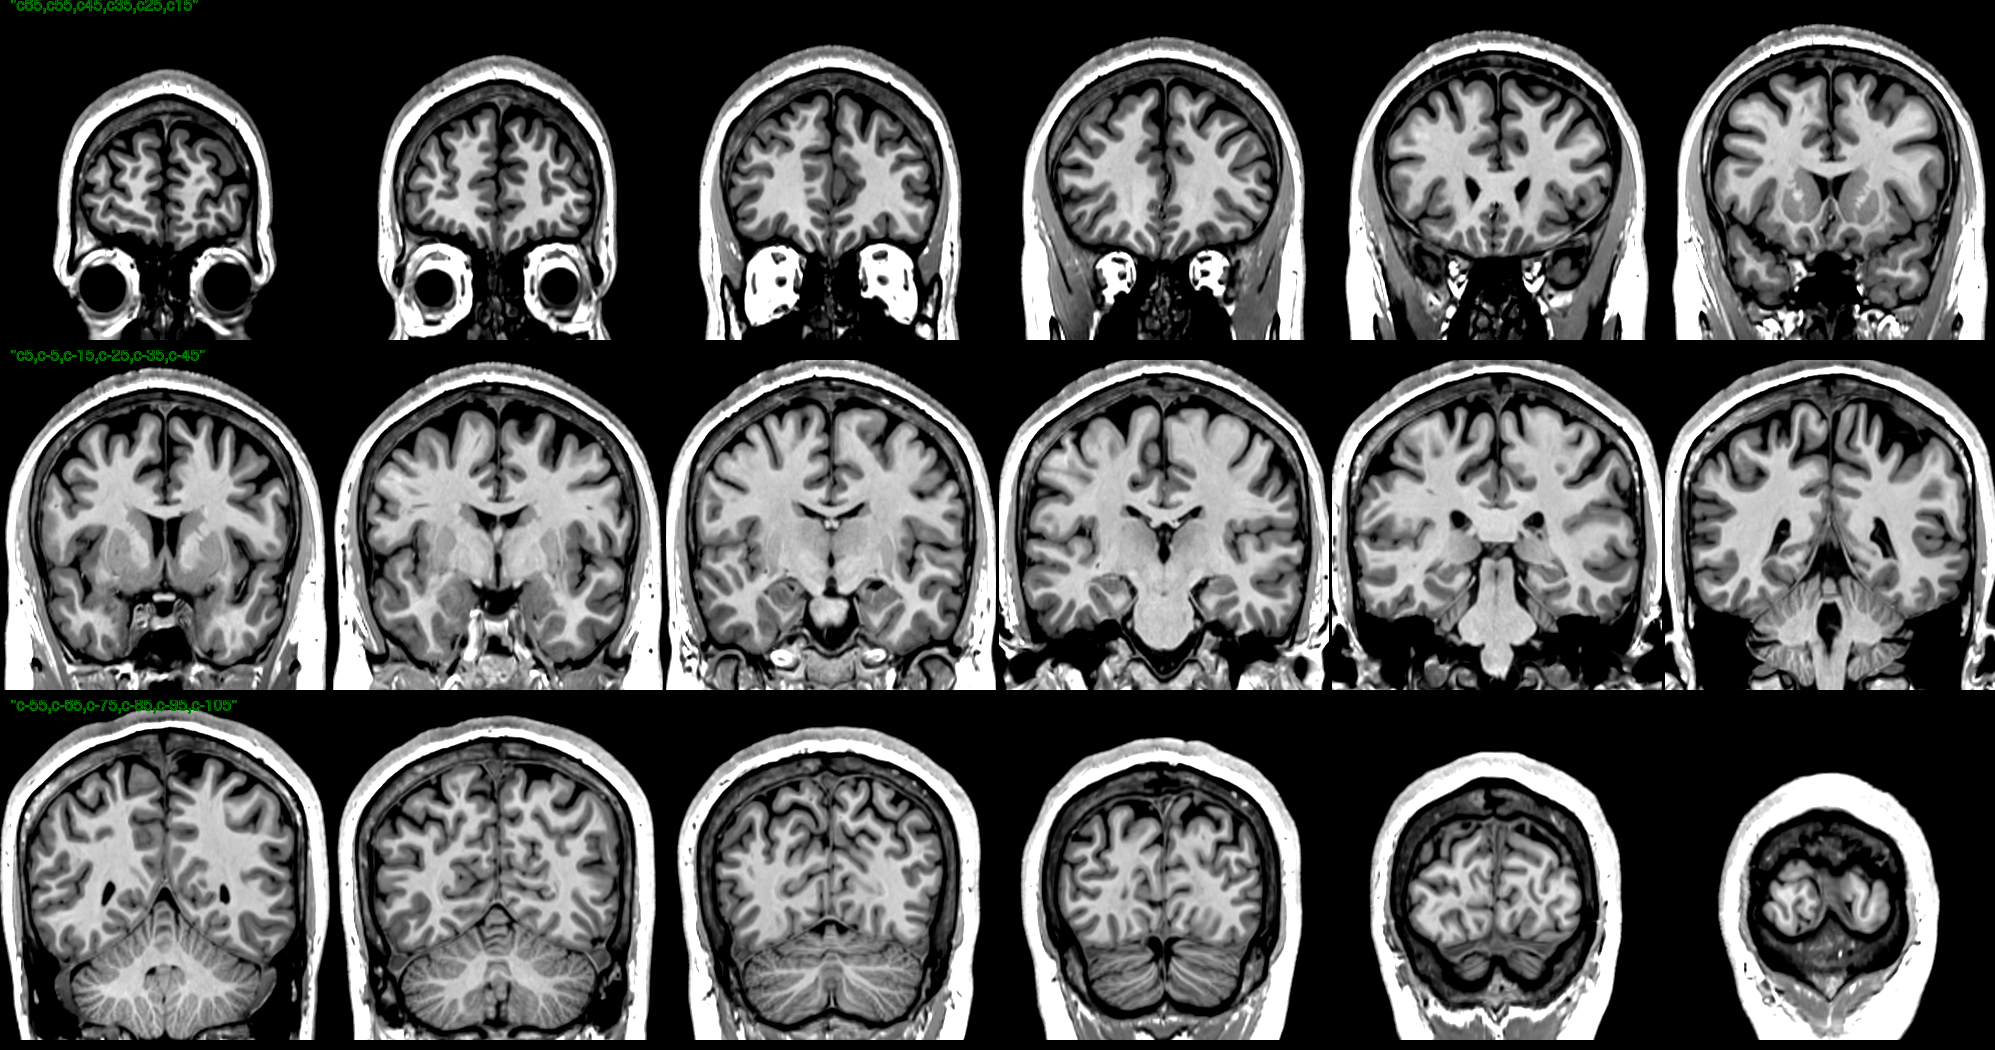

T1 Images